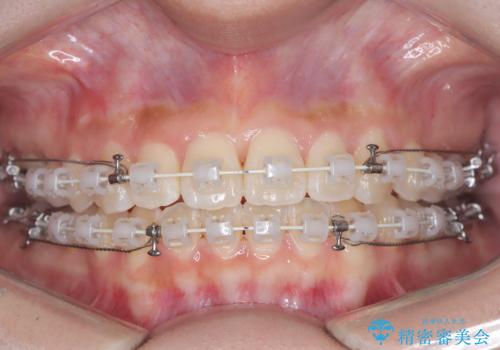

治療では、審美ワイヤーを使用し、目立ちにくく配慮しながら矯正を進めました。上顎にリンガルアーチと矯正用アンカースクリューを用いて臼歯部を安定的に遠心移動させ、歯列全体のスペースを確保しました。その後、回転していた前歯を正しい位置に配列し、全体的な歯並びの改善を行いました。治療中は、装置の適切な管理と口腔衛生を徹底することが重要でした。結果として、見た目だけでなく機能的にも優れた歯列を実現することができ、患者様にもご満足いただけました。